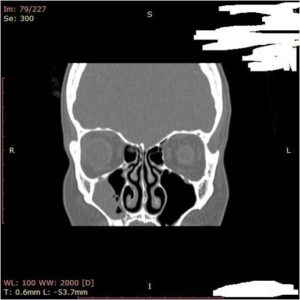

- Придаточные пазухи носа

- Кость верхней челюсти участвует в формировании придаточных пазух носа и глазницы